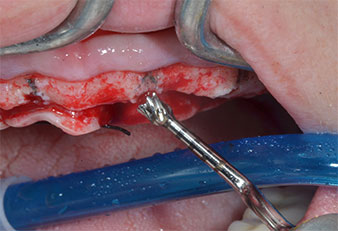

Para marcar las posiciones del implante y realizar la preparación piloto, se utilizó un inserto piezoeléctrico (Piezomed I1) con revestimiento de diamante y forma de llama (figura 3). Se tomaron precauciones para realizar movimientos hacia arriba y hacia abajo, con una potencia reducida, una irrigación completa y una baja presión (por debajo de 300 g). A continuación, se aplicó un inserto piloto (Piezomed I2A/I2P) para aumentar el diámetro inicial de 2 mm de los sitios de implante (figura 4), seguido de un inserto de 3 mm (Fig. 5).

Fig. 4: El siguiente paso fue el aumento piloto con los insertos I2A/I2P, que se aplicaron con un movimiento rotatorio horizontal.

En casos de huesos densos, es preciso utilizar toda la secuencia de insertos, incluidos los insertos intermedios Piezomed Z25P y Z35P, pues esto permite ampliar las osteotomías antes del siguiente paso de ampliación.

Tales insertos también están indicados para la preparación cerca de la membrana del seno en combinación con los procesos de elevación interna, así como cuando hay menos de 4 mm de altura de hueso residual.

En el caso que nos ocupa, no se utilizaron los insertos Z25P ni Z35P debido a la existencia de un hueso posterior relativamente blando, que se trató sin problemas con el I3A/I3P.